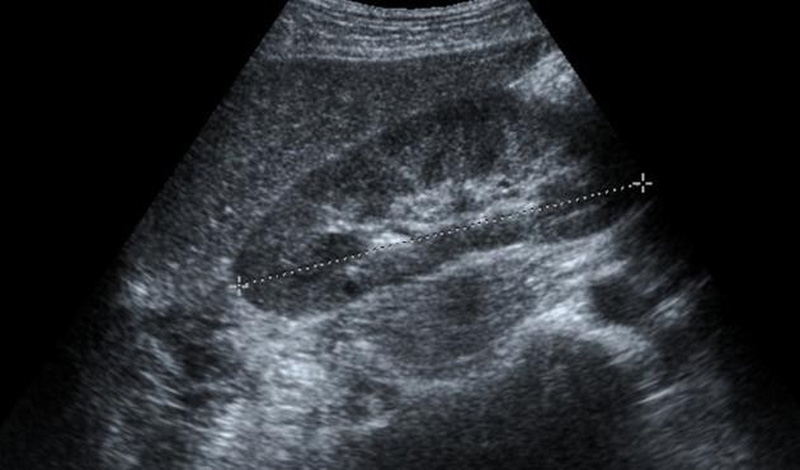

Khi hình ảnh siêu âm gan bất thường, có thể bác sĩ sẽ chỉ định xét nghiệm viên gan B